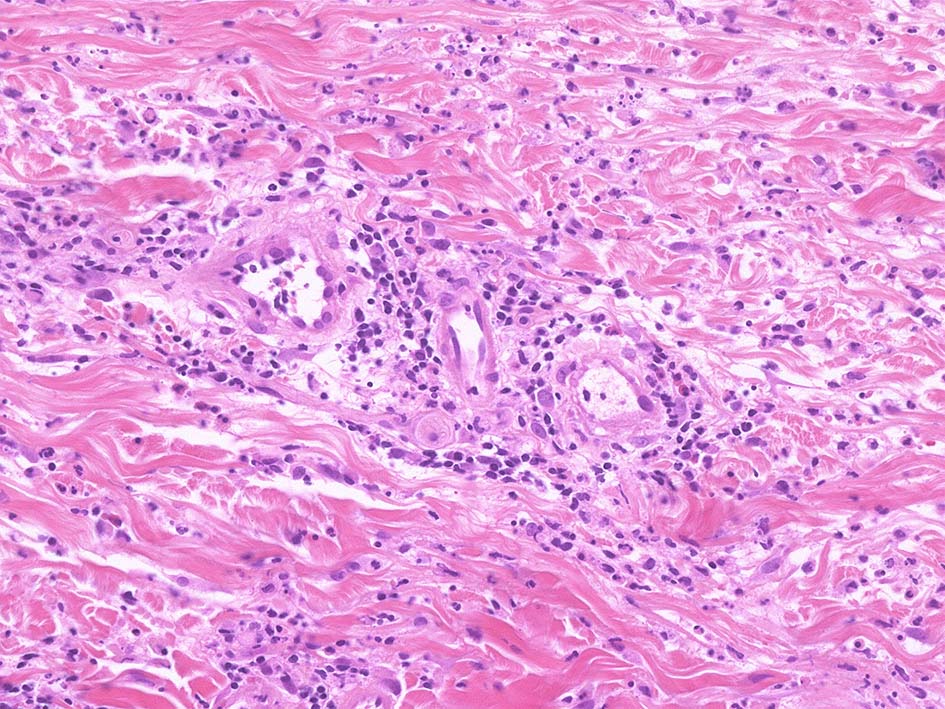

Case02 前胸部皮膚

73 year old male

骨髄異形成症候群で入院中. 発熱, 関節痛に加えて四肢, 胸部など上半身に潰瘍形成をともなう浮腫性紅斑が出現してきた. 皮下硬結あり. Sweet症候群と診断.

中央に黒色痂皮を示す紅斑. 硬結の強い部位から生検される.

HE x40. 表皮下水疱あり. 真皮上層は浮腫状. 真皮から皮下組織にかけて, 多数の好中球が浸潤している. リンパ球, 好酸球が混在, 核破砕物を貪食するマクロファージが増加. 膠原線維にはところどころ変性が見られる.

真皮上層には核破砕物が多く, 好中球浸潤が認められる. 慢性炎症性細胞も浸潤している.

フィブリノイド壊死を呈する血管炎は認められない.

皮下脂肪織炎病変には局所的なhemophagocytosisが認められる. 血管にはfibrinoid necrosisは見られない。